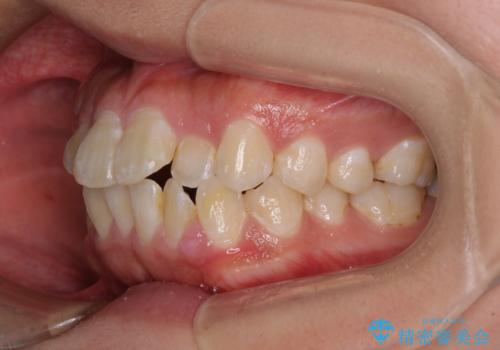

- 前歯のクロスバイトと、口元が閉じにくいとのことで来院された患者様です。

口元の突出感を改善する必要があるため、上下左右の第1小臼歯4本を抜歯し、ワイヤー装置にて矯正治療を行うこととしました。

むし歯のリスクが高かったため、治療が長期化しないように心がけました。

当初の予定通り、2年強で無事に治療を終えることができました。